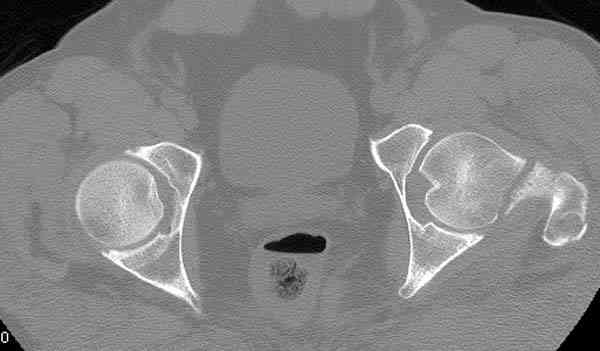

На второй день (7) обнаружен пропущенный перелом,

сделаны Компьютерная Томограмма

и проведены шурурпы через и спереди штифта без удаления.